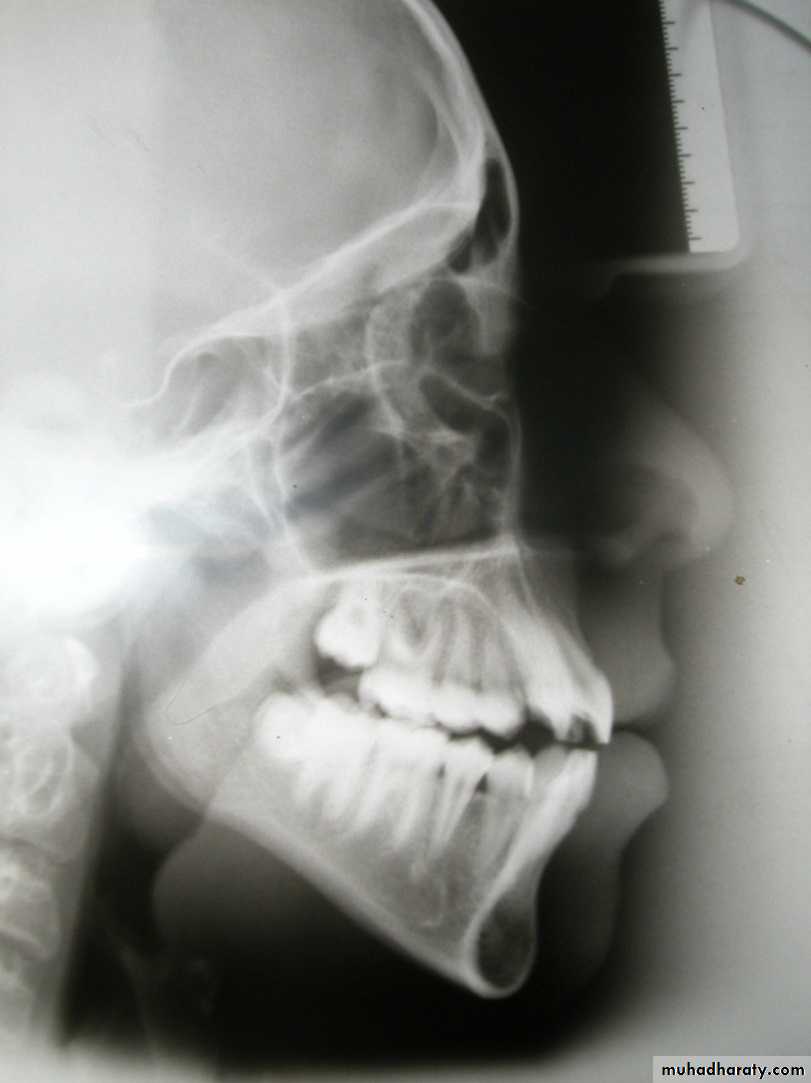

Antero-posterior skeletal relations

SNA angle (82 + 3)

Indicates antero-posterior position of maxillary apical base in relation to the cranial base: Large angle = Prognathic maxilla

Normal angle = Orthognathic maxilla Small angle = Retrognathic maxilla

SNB angle (79 + 3)

Indicates antero-posterior position of mandibular apical base in relation to the cranial base

Large angle = Prognathic mandible

Normal angle = Orthognathic mandible

Small angle = Retrognathic mandible

ANB angle (3 + 1)

Indicates the skeletal relationship between maxilla and mandible:

Large angle = postnormal relation (skeletal class II)

Normal angle = Normal relation

(skeletal class I)

Small angle (reverse) = Prenormal relation (skeletal calss III)